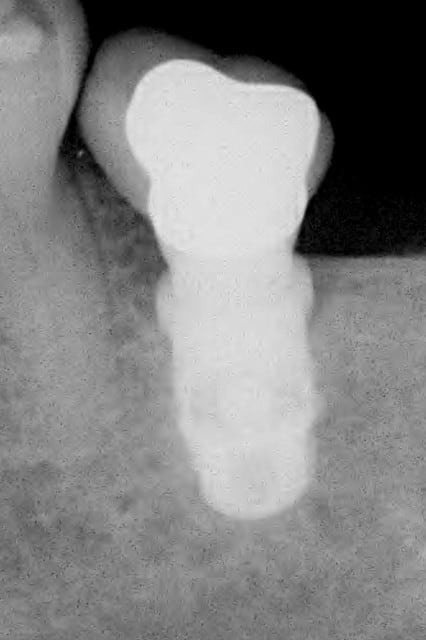

Je l'ai utilisé il y a 5 ans sur une canine en potection totale (Pas le choix car en classe 2- 2).Depuis c'est la PM derrière qui a laché. Je te joins la RX.

Rx implant cad 2 cpyqbp - Eugenol

Meme les molaires ?! Moi je pensais justre aux PM. En tout cas ta canine a l'air parfaite. Ca ouvre des perspectives, merci de ta réponse.

rx à j=0 et j+4 mois

ce qui est surprenant , c'est la présence d'os au niveau du col.

Oui on connait chez Leone mais reproductible sur toute la gamme. C'est qu"est que je dit! Mais nous c'est démontable et indexé. Un vieux cas en rx 5 ans entre les deux rx.